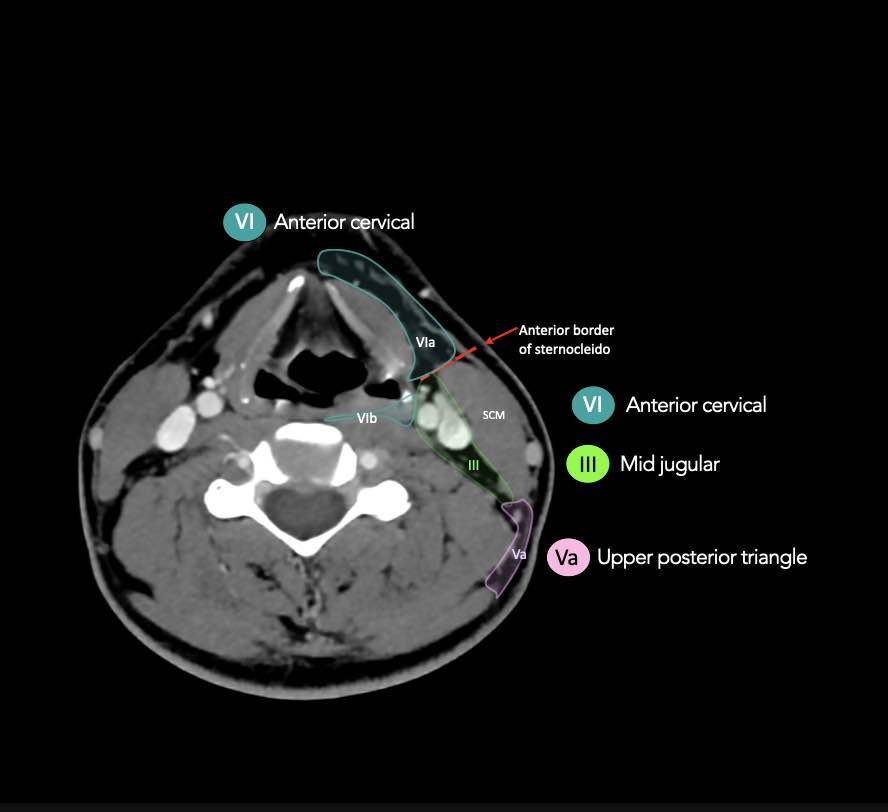

CT Scan Mặt Cắt Ngang (Axial CT)

Các lát cắt CT mặt phẳng ngang tương ứng với hình minh họa tổng quan.

Các lát cắt CT mặt phẳng ngang với hình ảnh chi tiết hơn.

Nhấp vào hình ảnh để phóng to.

VI – Cổ trước

Tầng này chứa các hạch tĩnh mạch cảnh trước nông (tầng VIa) và các hạch sâu hơn bao gồm hạch trước thanh quản, trước khí quản, cạnh khí quản và hạch thần kinh thanh quản quặt ngược (tầng VIb).